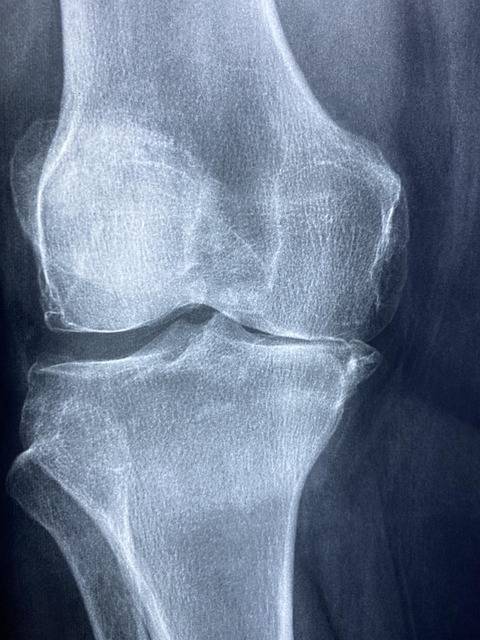

1. 관절염 완화

꿀과 계피의 조합은 관절염 통증 완화에 효과적입니다.

덴마크 코펜하겐 대학의 연구에 따르면, 꿀과 계피를 매일 아침 식사 전에 섭취한 관절염 환자 중 73%가 통증이 완화되었으며, 한 달 후에는 대부분의 환자가 통증 없이 걸을 수 있었다고 보고되었습니다.

꿀에 포함된 플라보노이드 성분은 항산화 작용을 통해 염증을 억제하고, 계피의 신남알데히드 성분은 항염 효과를 강화하여 관절 건강에 도움을 줍니다.